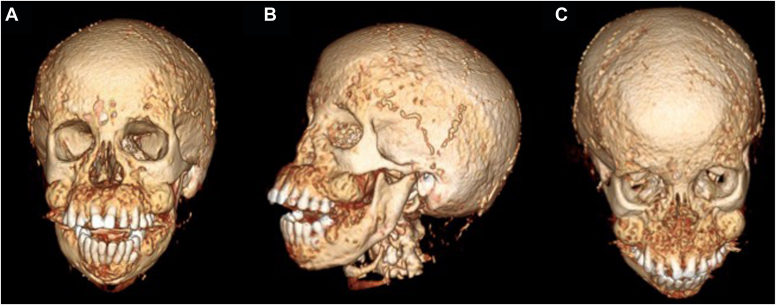

A 48-year-old woman with a history of hypertension, coronary artery disease, and ESRD on hemodialysis presented with severe secondary hyperparathyroidism and calciphylaxis. She had significant changes to her face in the last 3 months leading to oropharyngeal dysphagia and difficulty articulating. Physical examination revealed bony overgrowth in her upper jaw and hard palate, widely spaced teeth, and calcinosis cutis. Her parathyroid hormone (PTH), calcium, and phosphorus levels were 5066 pg/mL (normal range, 12-88 pg/mL); 10.0 mg/dL (8.4-10.2 mg/dL); and 5.4 mg/dL (2.7-4.5 mg/dL); respectively. Using a multidisciplinary approach, she successfully underwent a 3.5-gland parathyroidectomy (immediate postoperative PTH level, 600 pg/mL). She was discharged without complication. Pathology showed hypercellular parathyroid glands with reactive changes.

ULO, the most severe form of renal osteodystrophy, results in hypertrophy of the craniofacial skeleton. It carries the risk of significant comorbidities due to cranial nerve compression, respiratory compromise, dysarthria, and dysphagia.